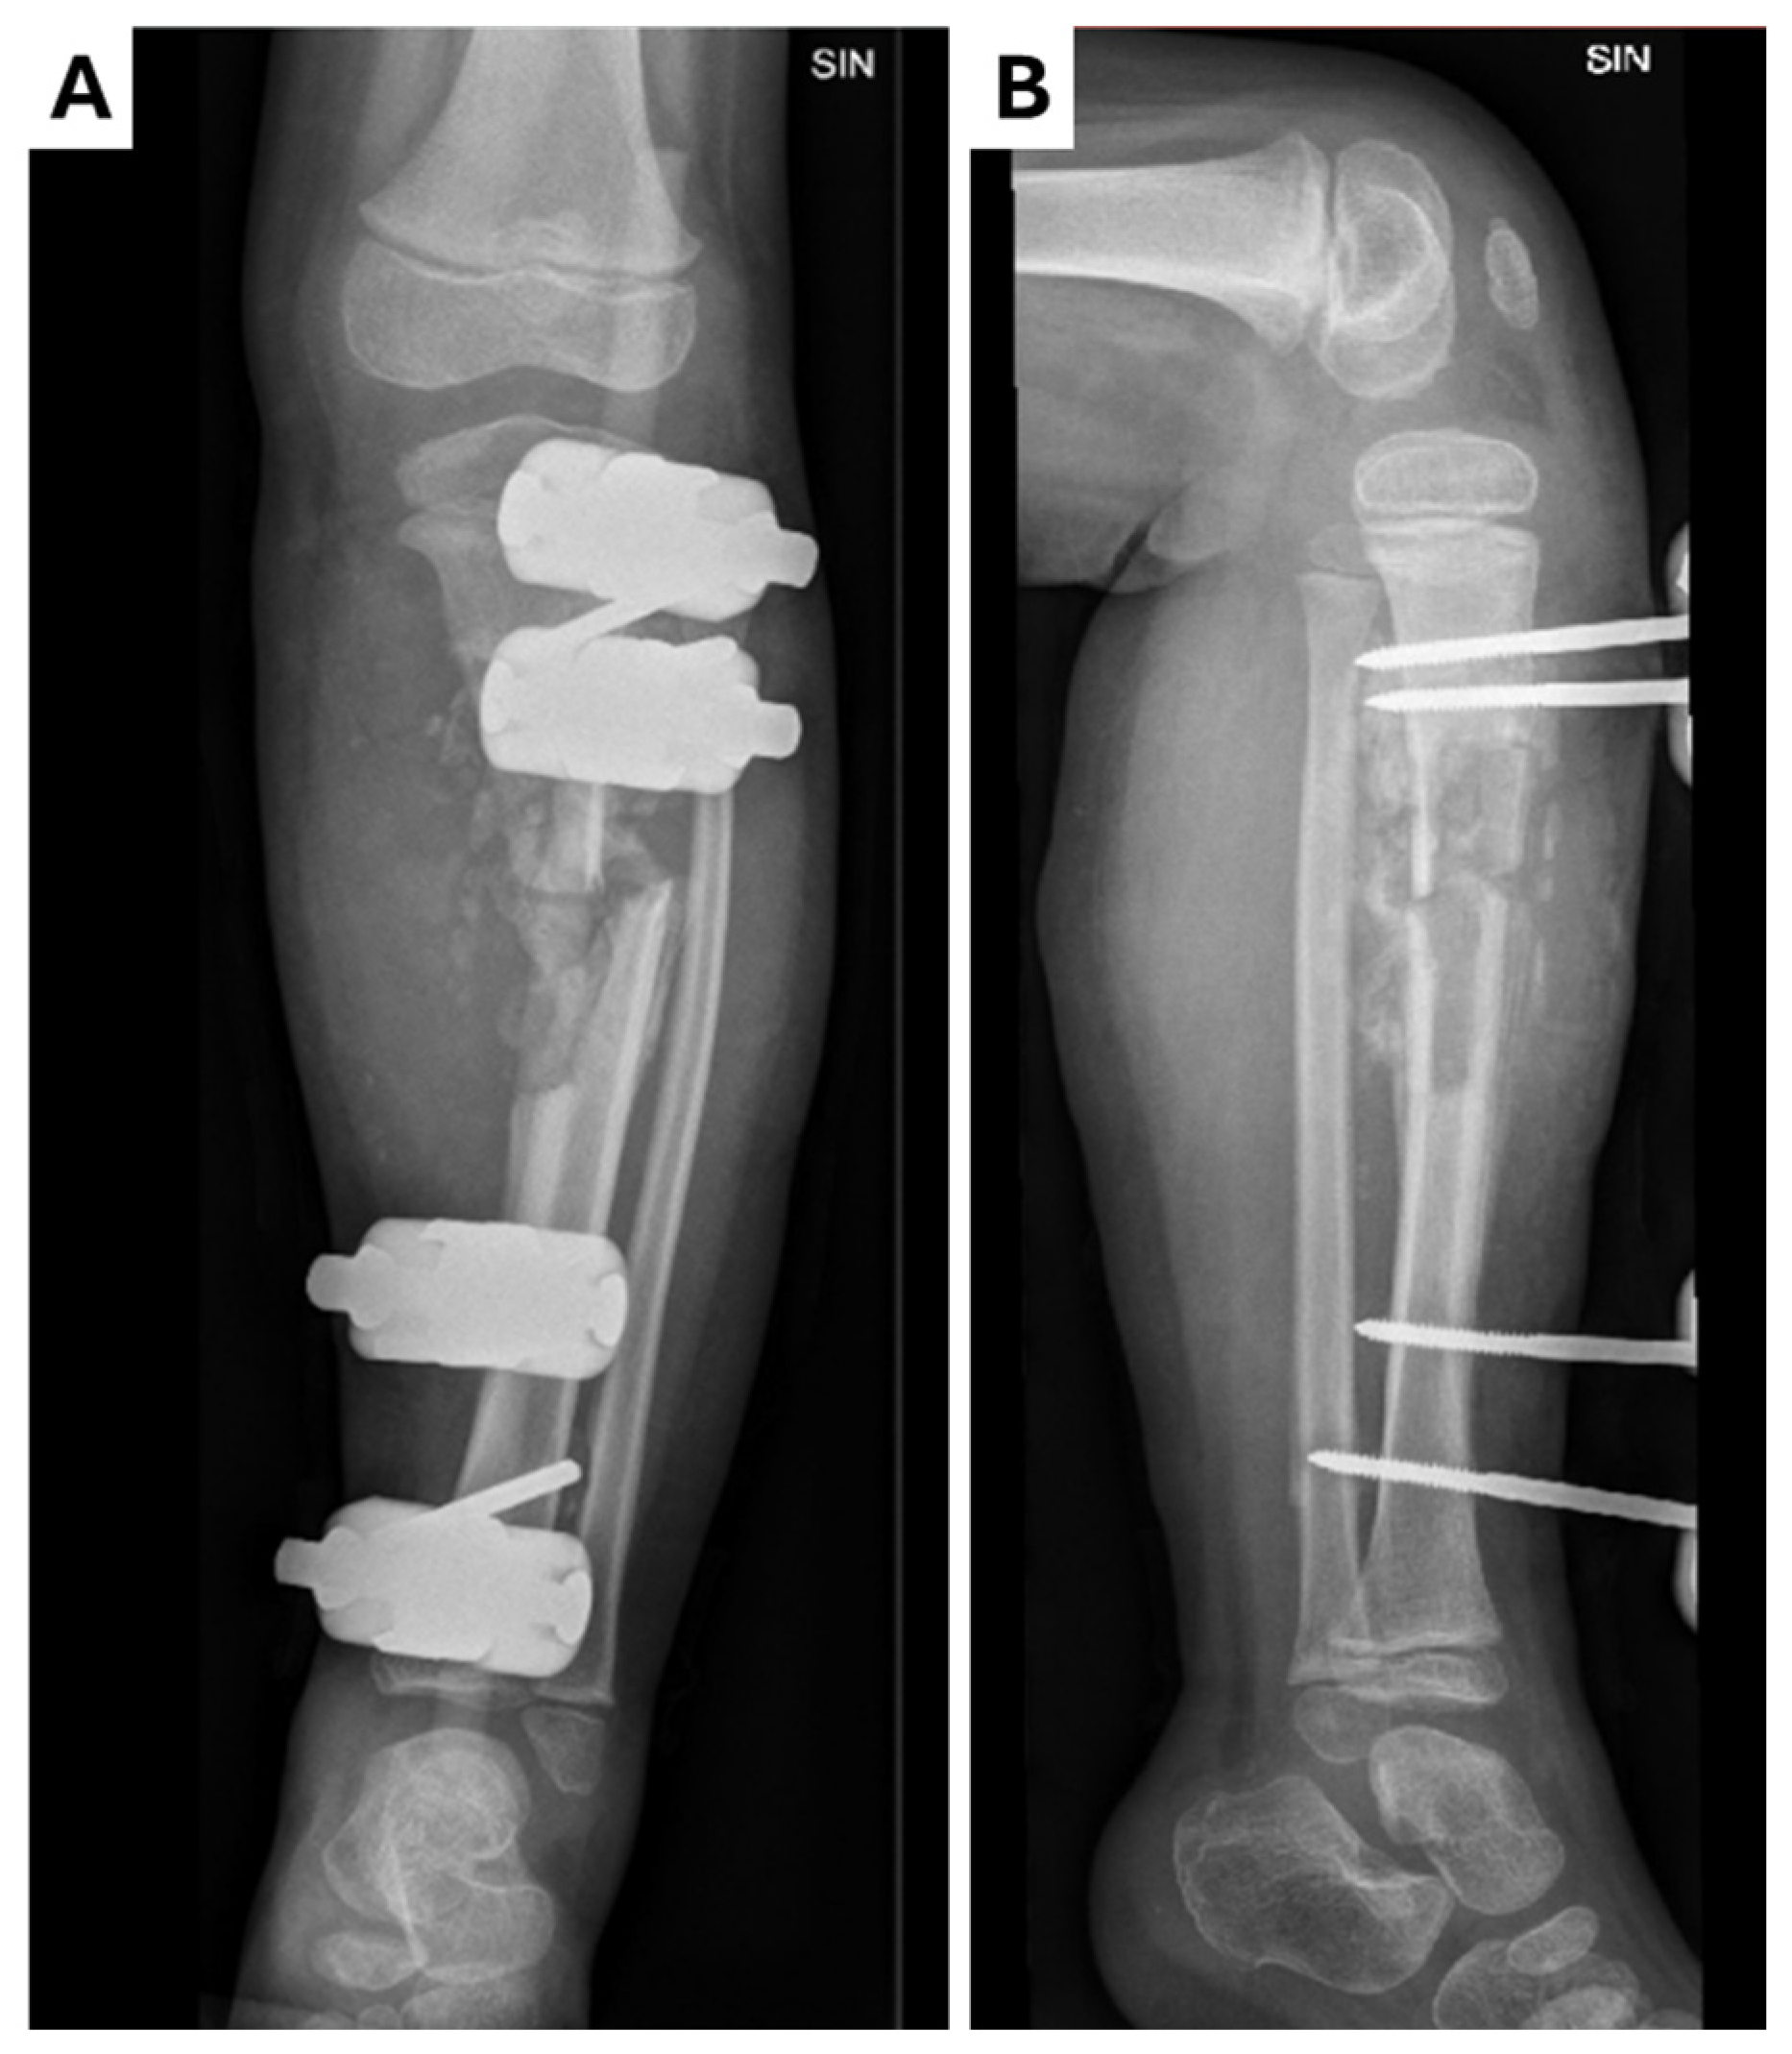

Figure 2.

Control X-ray of left leg in (A) anterior–posterior and (B) lateral projections after surgical manipulation and external fixation. During surgery, the rotation of the medial part of the tibia toward the fracture was performed along with the drainage of pus (~500 mL) around the fracture site. Pseudoarthrosis was observed during surgery along with the presence of infected cartilage tissue. Resection of the damaged bone was performed, resulting in limb shortening (~1 cm). A chlorhexidine impregnated material was left in the wound.